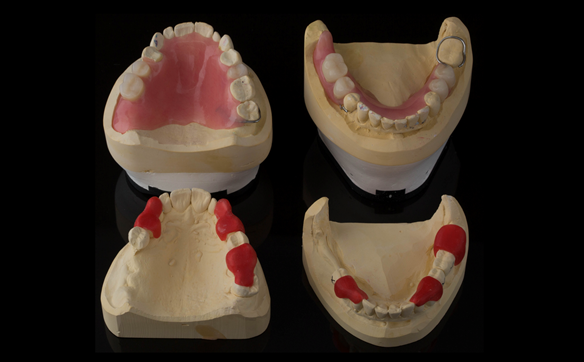

This newsletter describes in step by step detail Angela's transition through immediate partial dentures to crown supported definitive metal based dentures.

The clinical situation and treatment process is shown in detail below with photographs. I (Finlay Sutton) provided the clinical work and Rowan Garstang provided the technical work.